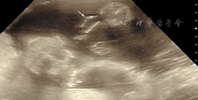

病例1,孕妇26岁,孕1产0,孕32周,平素月经规律,否认家族性遗传病史。孕期曾在外院行产前超声检查未见异常。因阴道流液1 d余,入我院行超声检查,胎儿生长参数与孕周相符。胎儿头皮水肿增厚约0.69 cm,颅内结构、心肺未见明显异常,胎儿胃、膀胱、双肾、脊柱可显示,羊水最大平段12.5 cm,羊水指数43.1 cm。胎儿两侧眼眶上方分别可见1.7 cm×0.9 cm、1.8 cm×1.1 cm的混合性回声肿块,肿块突出于体表(图1)。双眼及晶状体回声可见,下颌短小且内收,嘴唇呈微张状。动态观察,嘴唇未见闭合,舌头位于上下唇之间,双手呈握拳状,双足短小且姿势异常,足底皮肤厚约1.0 cm。羊膜腔内可见多条带状回声(图2)。超声提示:①单活胎,头位﹔②羊水过多﹔③胎儿头皮水肿,颜面异常,双侧眼眶上方软组织肿块﹔④胎儿双手及双足短小、姿势异常﹔⑤羊膜腔内多条带状回声。引产一女婴,大体标本见婴儿全身被一黄色角质样物质包裹,呈皲裂状,以头、面、颈、躯干、外阴部最明显;双唇增厚水肿外翻,牙槽外露;无鼻骨鼻翼,仅见两个鼻孔;眼睑外翻,双眼外上侧见两团红色肉样赘生物;小耳,仅有耳廓及耳孔,无耳道;小下颌;四肢呈弯曲状态,手足发育不全,脚掌呈"蹼形",指趾粗短,其关节肿大呈"兽爪样",外阴发育明显小于正常婴儿,肛门仅见裂隙。取小块黄色角质样物送病理检查提示角质层过度增厚,角化过度。根据临床表现及病理特征诊断:胎儿鱼鳞病。

此病胎儿全身皮肤增厚、皲裂,超声图像上显示胎儿皮肤呈"龟壳"样或"地图"样改变,尤以面部及头颅部皮肤显著。病例1超声显示羊膜腔内多条带状回声,为患儿皲裂的皮肤漂浮于羊水中。病例2属于轻型,故超声仅显示皮肤增厚。